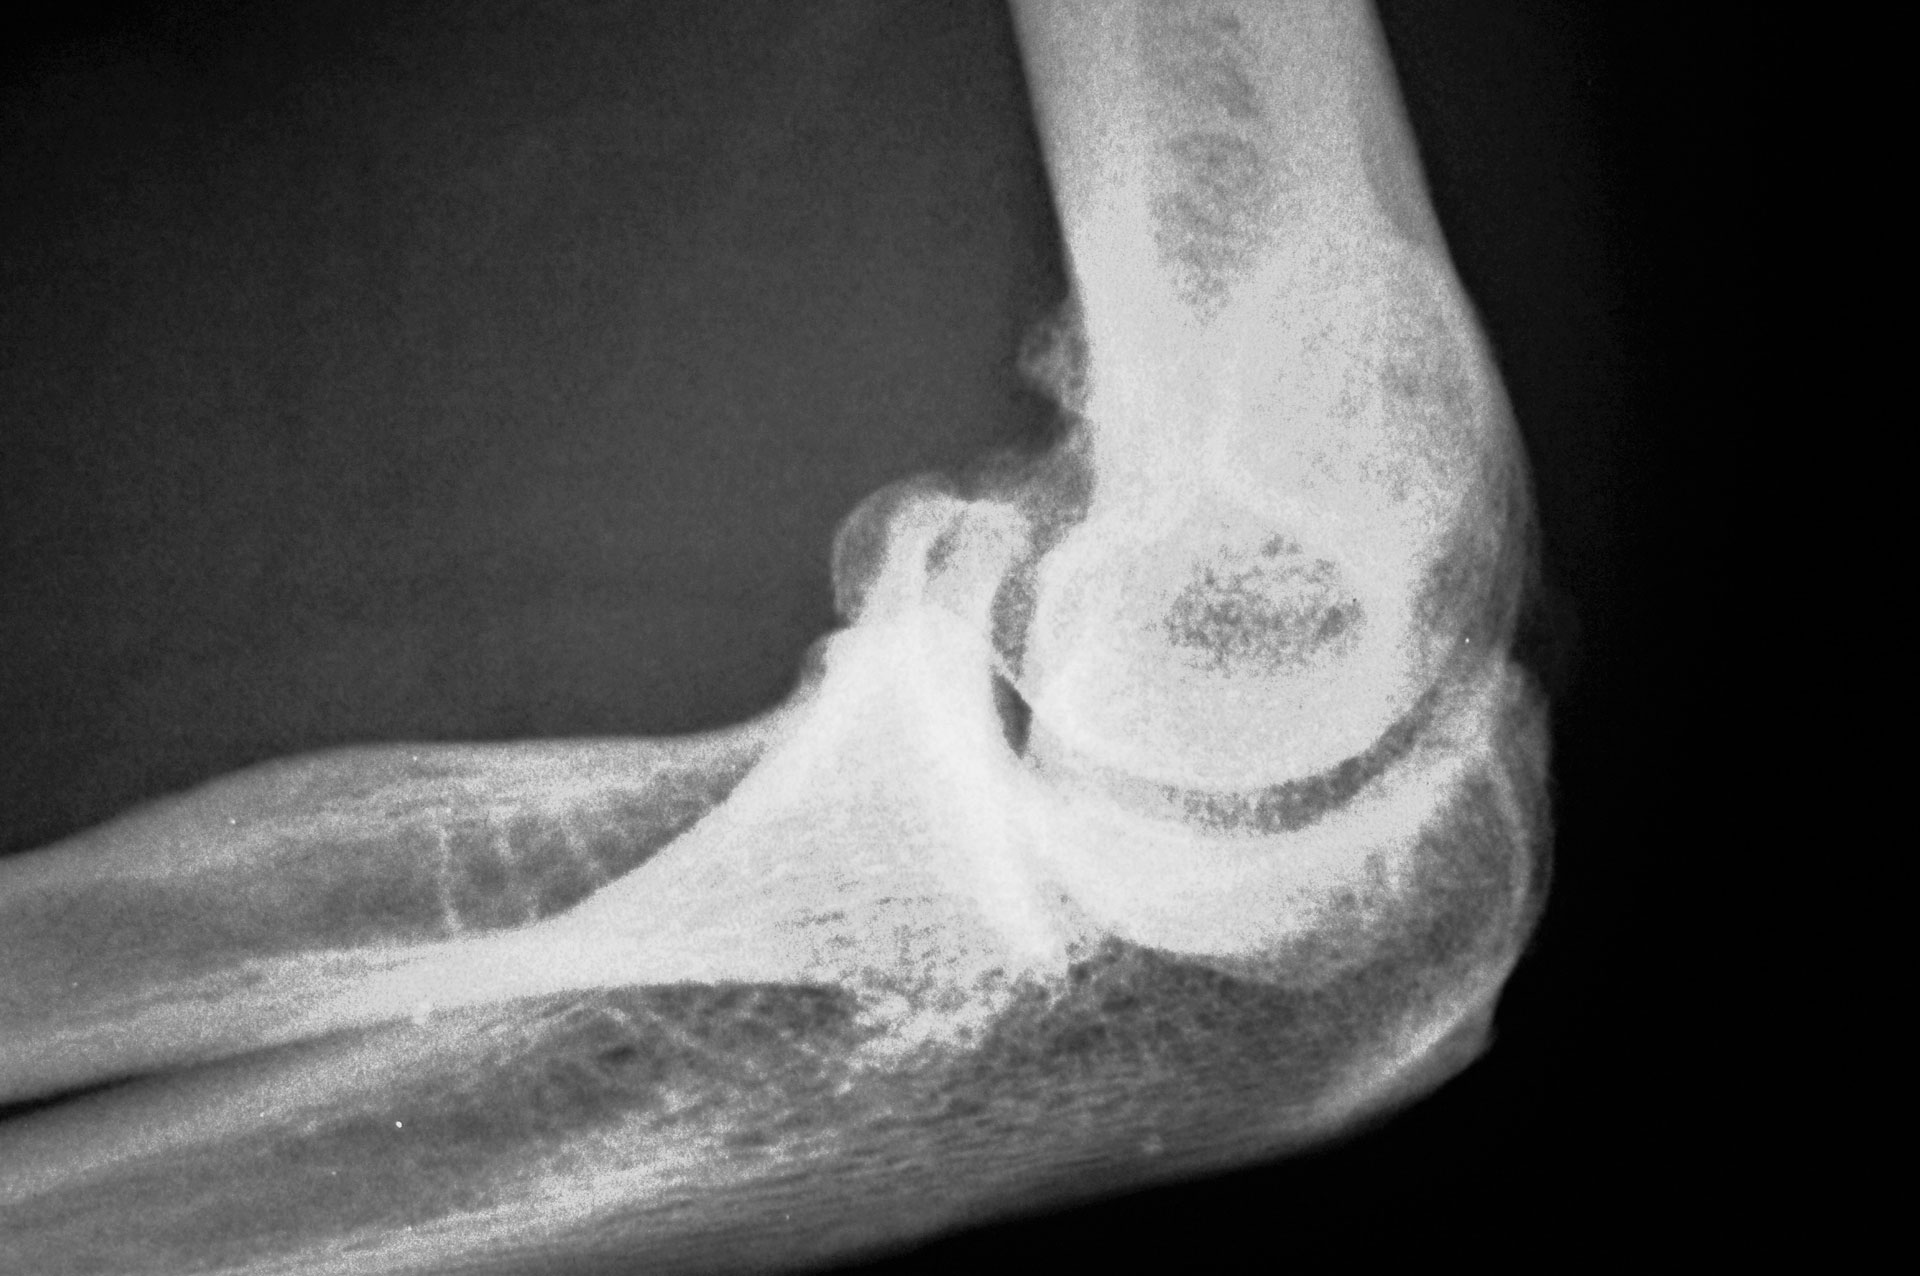

Μία άρθρωση «περιτριγυρίζεται» από συνδέσμους και τένοντες. Όταν αυτοί έχουν υποστεί βλάβη ή φλεγμονή, η ανάπτυξη του οστού επηρεάζεται και νέα οστικά κύτταρα δημιουργούνται και μεγαλώνουν σε σημεία που δεν πρέπει. Φανταστείτε τα οστεόφυτα σαν καρφιά πάνω στο οστό- έτσι φαίνονται στην ακτινογραφία- ενώ στην πραγματικότητα δεν είναι αιχμηρά αλλά στρογγυλεμένα.